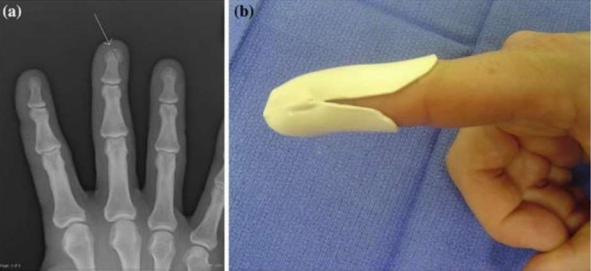

Figure 01 (a) This image shows a rotational malalignment of the ring finger (crossing over the small finger) from a fracture at the base of the proximal phalanx of the ring finger. Due to a fairly normal looking appearance of the hand with the fingers extended the injury was initially treated non-operatively. Notice the gap between the middle and ring fingers, and the deviation of the ring finger from the normal cascade. The patient was treated with an operative reduction and percutaneous pinning.

(b) A normal finger cascade with all fingers pointing toward the thenar eminence is seen in the same patient 4 weeks after surgery. Passive finger flexion is demonstrated using the tenodesis effect that occurs with passive wrist extension